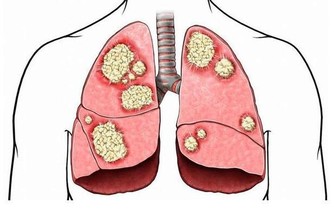

先來看看你的牙齦是不是已經是這樣了:

所以洗牙會出血那是因為你的牙齦已經發炎了!當結石碎裂脫離牙面時,

碰到有炎症的牙齦就會引起出血,所以洗牙時出血多少也是反應炎症嚴重程度的一個指標。